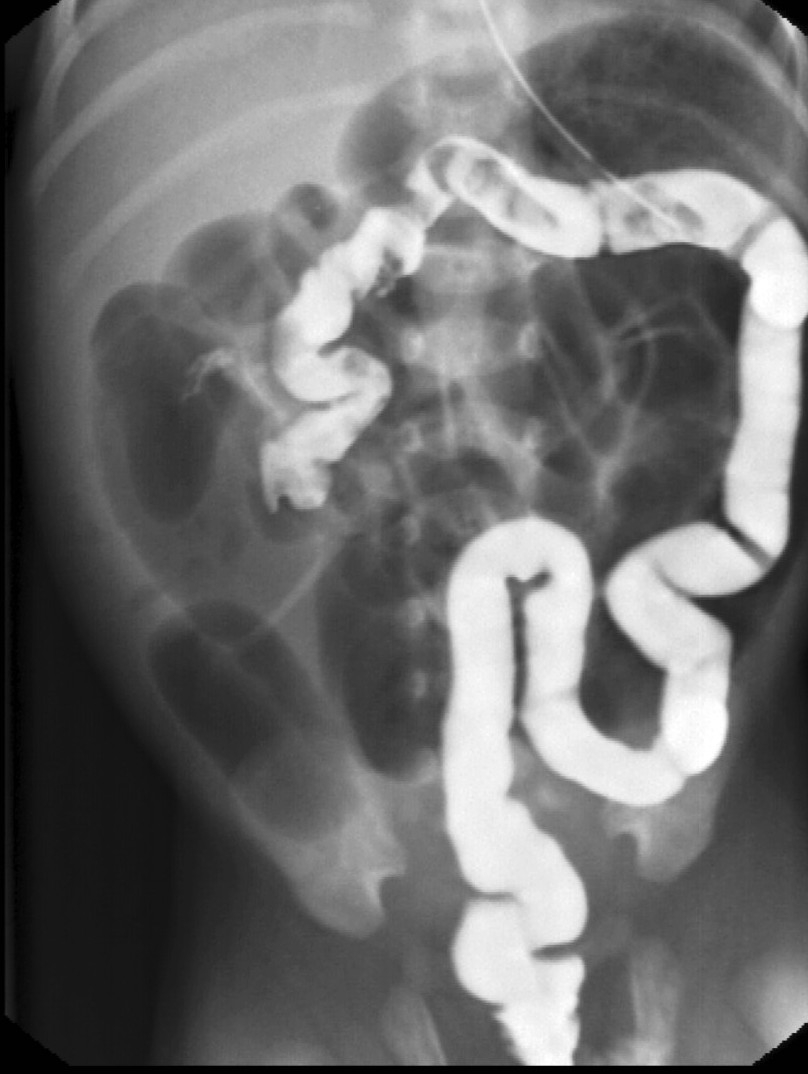

Image

15. Contrast material empties the stomach slowly, small intestines are found on the right side of the abdomen. Malrotation-volvulus.